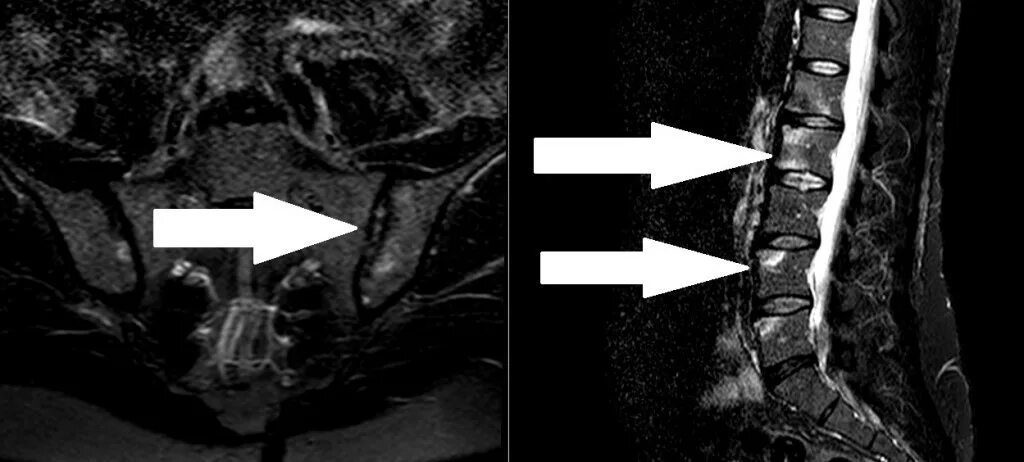

Просмотр снимков мрт